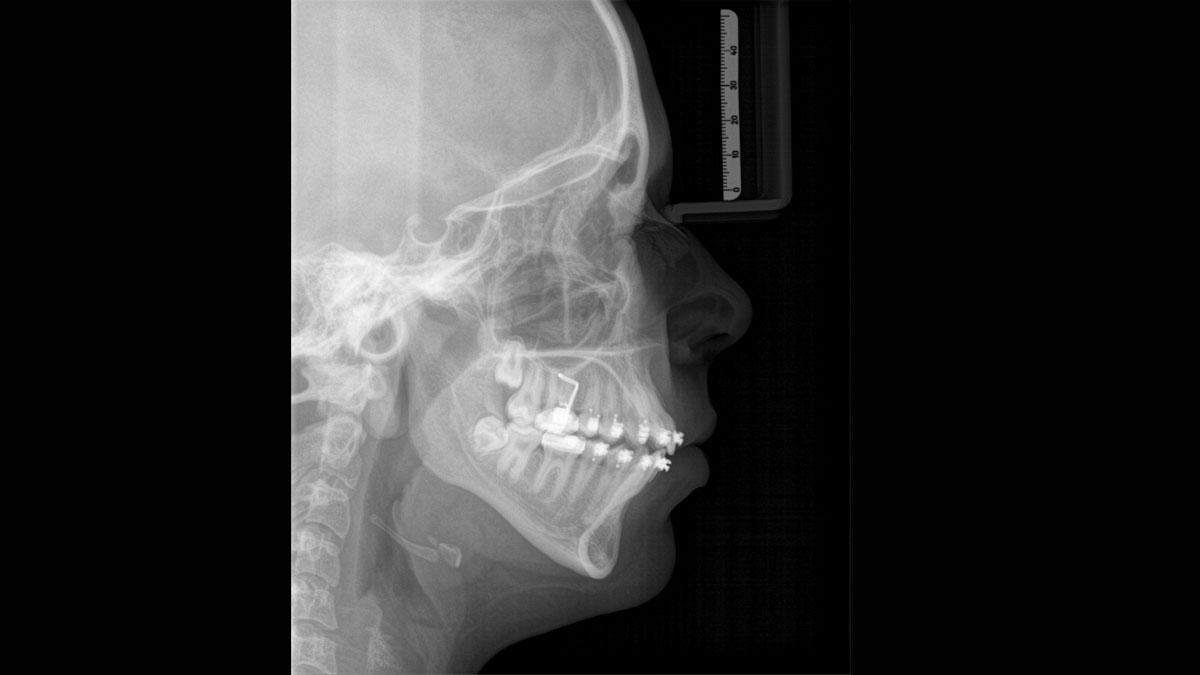

Sefalometrik Görüntüleme

Orthophos SL 2D ürünlerine istediğiniz zaman bir sefalometrik kol takılabilir. Röntgen odanıza sığdığından emin olmanız için, kol ünitenin sağ veya sol tarafına monte edilebilir.

Tüm ortodontik ihtiyaçlarınızı karşılayan sefalometrik programlar

Özel bir sensör yardımıyla, lateral ve simetrik p.a. veya a.p. ve ayrıca karpus (el bileği) görüntüleri alabilirsiniz. Yerinden çıkmış dişler için, tam konumlarını belirlemek üzere 3D röntgenleri de kullanabilirsiniz.

Örnek sefalometrik görüntü galerisi